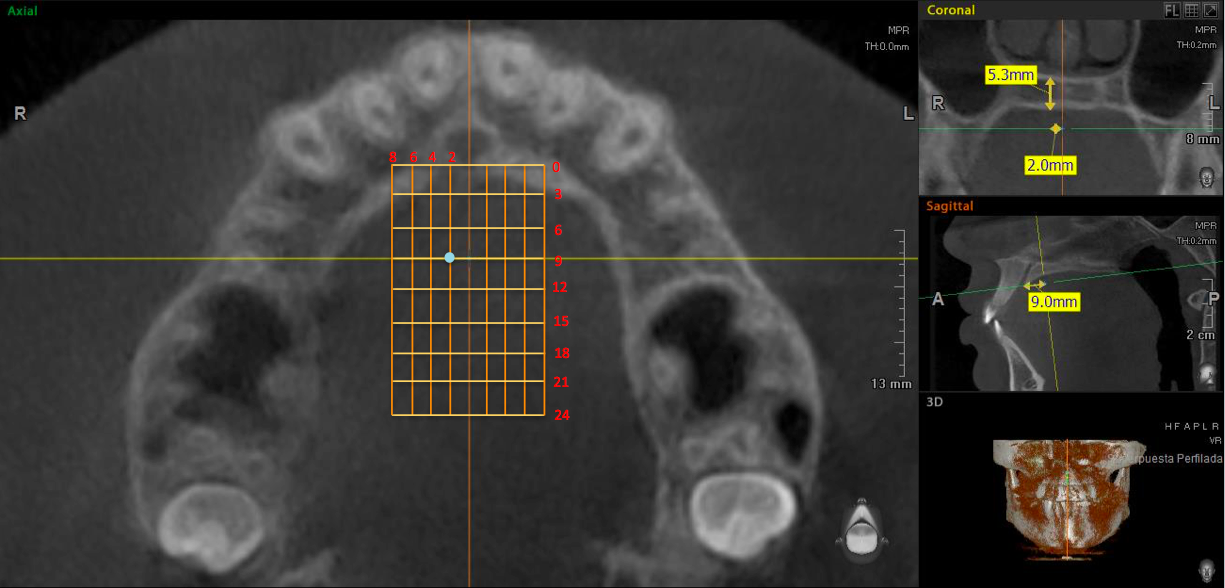

Posteriormente, en el corte coronal (Figura 3), perpendicular al plano axial se tomaron las medidas del grosor palatino en cada uno de los puntos de intersección de las líneas de referencia antes mencionadas, formando una cuadrícula de 72 sitios (Figura 4). Así, en las Figuras 3 y 4 se observa el grosor palatino de 5.3mm a los 2mm (sagital) y 9mm (coronal) del lado derecho.

Cuadrícula del paladar. Grosor palatino de 5.3mm a los 2mm (sagital) y 9mm (coronal) del lado derecho